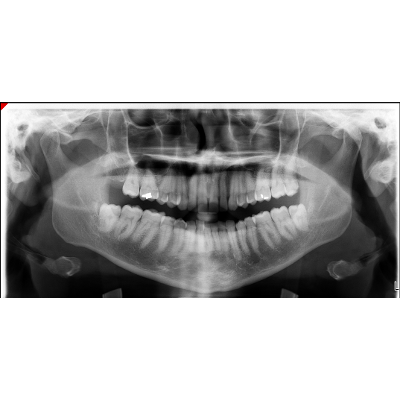

Prescription medication and oral radiographic examinations during pregnancy

It is an ebook covering dental care for pregnant and postpartum women. Educational goal: to present the indications and restrictions of medical dental treatments in the gestational and postpartum period as well as radiographic exams and fluorotherapy.